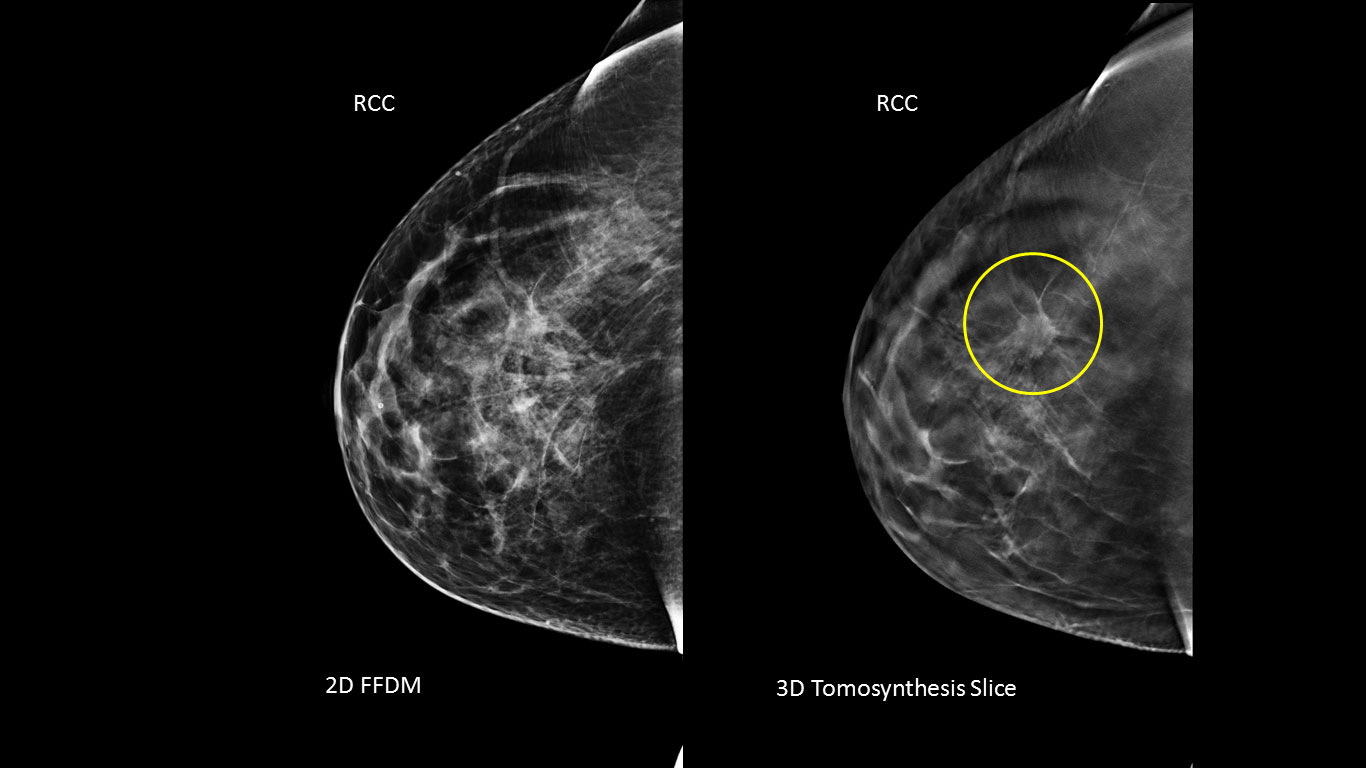

While digital (2D) mammography is considered one of the most advanced breast cancer screening technologies available today, it provides only a two-dimensional picture of the breast. The breast is a three-dimensional object composed of different structures, such as blood vessels, milk ducts, fat, and ligaments. These structures, which are located at different heights within the breast, can overlap and cause confusion when viewed as a two-dimensional, flat image. This confusion of overlapping tissue is a leading reason why small breast cancers may be missed and normal tissue may appear abnormal, leading to unnecessary call backs.

Hologic 3D Mammography is the first and currently the only FDA approved 3D mammography system in the U.S. It has been shown in numerous clinical studies to significantly increase the detection of invasive breast cancers while simultaneously reducing recall rates across all patient populations and breast densities. This technology was approved for breast cancer screening and diagnosis in the U.S. in February, 2011 and has been available in countries recognizing the CE mark since 2008. Hologic's 3D mammography technology is in use in all 50 states and over 50 countries.